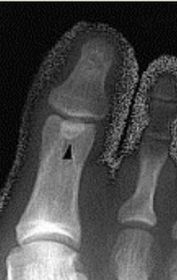

What is this? Where is it typically found? | Os interphalangeus. Typically found on the inferior aspect of the hallux IPJ. It is rare to see this ossicle at the IPJs of the lesser toes. |